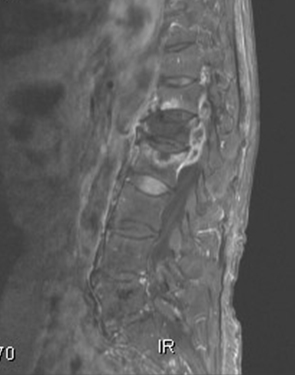

결핵성 골수염(Tuberculous osteomyelitis)

- 증상

-

관절통,

열,

근육경련,

식욕부진,

뼈의 변형,

체중감소

- 관련질환

골수염,

결핵성 수막염,

폐결핵,

속립성 결핵,

결핵성 임파선염,

결핵성 복막염,

위장관 결핵,

척추 골수염,

결핵

- 진료과

감염내과